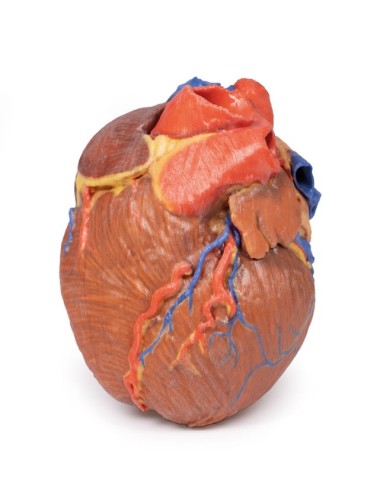

Modello anatomico di cuore, ingrandito 2 volte, su cavalletto

Questo modello dettagliato mostra, oltre alle strutture anatomiche del cuore, anche una parte del diaframma (base)